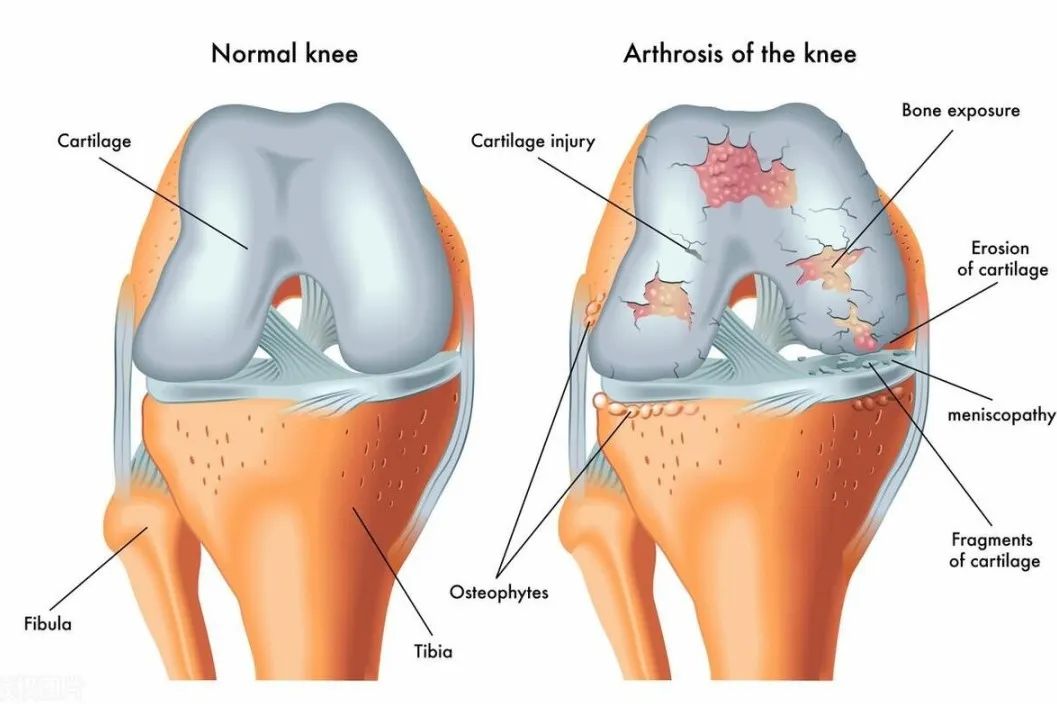

当一个人患上痛风后,上述的动态平衡被打破了,这是因为尿酸盐结晶刺激的炎症反应使局部的环境发生了变化,破骨细胞的活动被刺激增强了。不仅如此,血液中的某些细胞也在被刺激后发生改变,变得具有了和破骨细胞一样的能力,从而导致骨代谢失去了平衡,骨的侵蚀破坏更加严重。

当然,痛风患者的骨破坏是有很多因素共同参与的一个复杂过程,但是尿酸盐结晶刺激下的炎症反应在这种骨破坏机制中具有重要的作用。目前普遍认为,尿酸盐结晶是痛风骨质破坏的最重要、最直接的因素。

一些临床观察发现,在无症状的高尿酸血症期,骨关节同样会发生一些异常变化。通过超声检查,研究者发现,无症状高尿酸血症患者的关节也有与痛风性关节炎相同的一些改变,比如B超下的“双轨征”,即尿酸盐结晶在软骨表面沉积的超声特征;微小的痛风石;还有一些非特异性的超声特征,如骨侵蚀、滑膜炎、关节腔积液等。虽然单纯高尿酸血症期还没有痛风性关节炎的症状表现出来,但是关节内的病变已经在慢慢开始,到真正爆发出来只是需要等一段时间或一个契机。